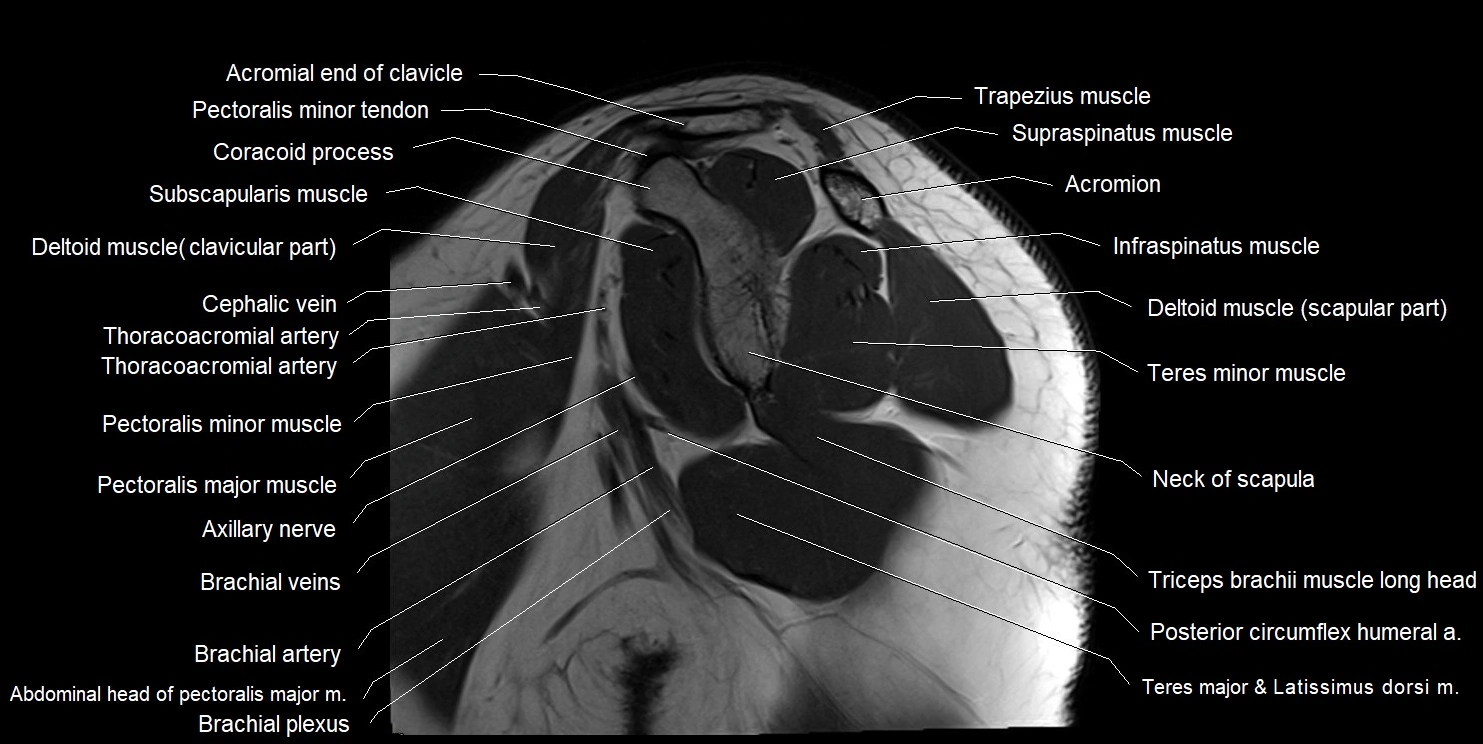

CT image

image